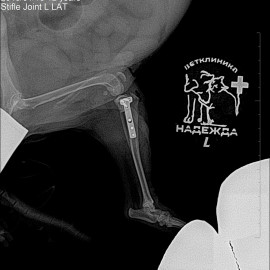

Пациент возрастом 12 лет породы йоркширский терьер по кличке Чупа.

Обратились к нам с жалобами на хромоту. На левую тазовую конечность.

После проведенных исследований был поставлен диагноз: разрыв передней крестообразной связки левого коленного сустава. Была проведена операция: TPLO.

Снимок 2 после операции.